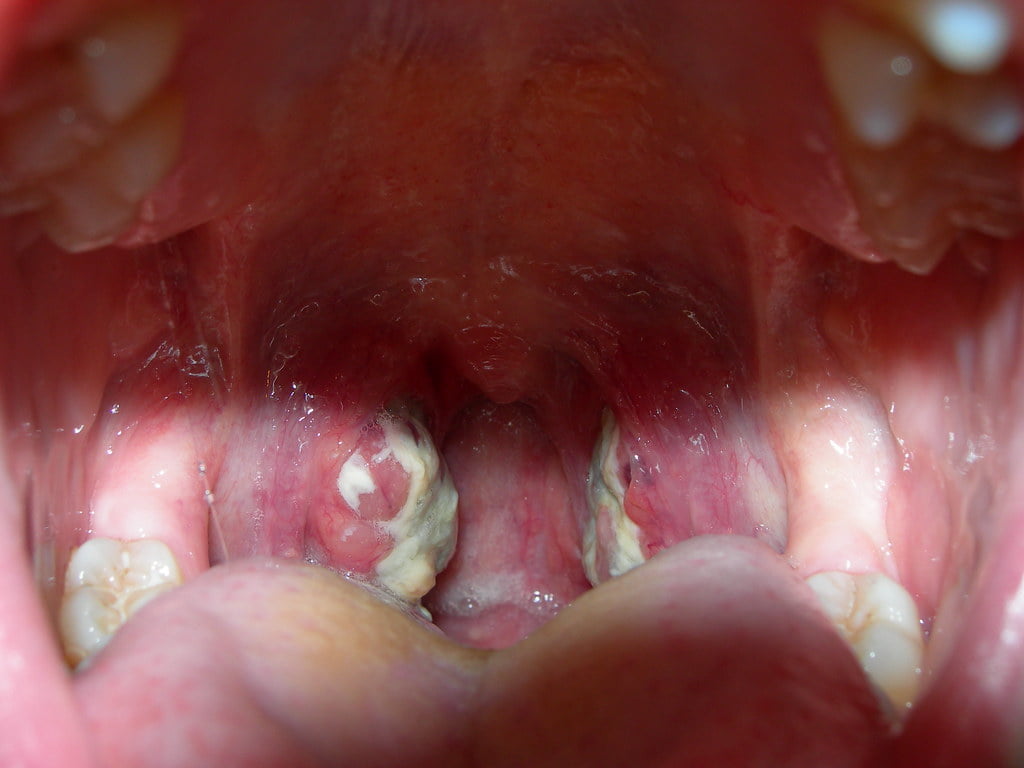

Atât copiii dar și adulții pot suferi de boli de focar. Cele mai multe amigdalectomii se fac la copii. Exemple de boli de focar pot fi: pericardita, glomerulonefrita, endocardita, poliartrita reumatică, miocardita, etc. Amigdalita de focar este diferită de amigdalita cronică. În cazul acesteia din urmă amigdalele sunt mici, se fixează cicatricial de țesuturile din jur, au colorit ruginiu-roșiatic, au cripte amigdaliene cu lichid cu microbi și leucocite, apar ganglioni tumefiați în zona subangulomandibulară; starea persoanei este în general alterată, pare foarte obosită și palidă.